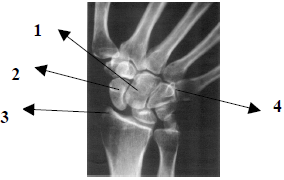

Observe atentamente a imagem radiográfica abaixo e em seguida responda a questão.

Pela anatomia radiológica demonstrada na imagem, podemos afirmar que trata-se da incidência